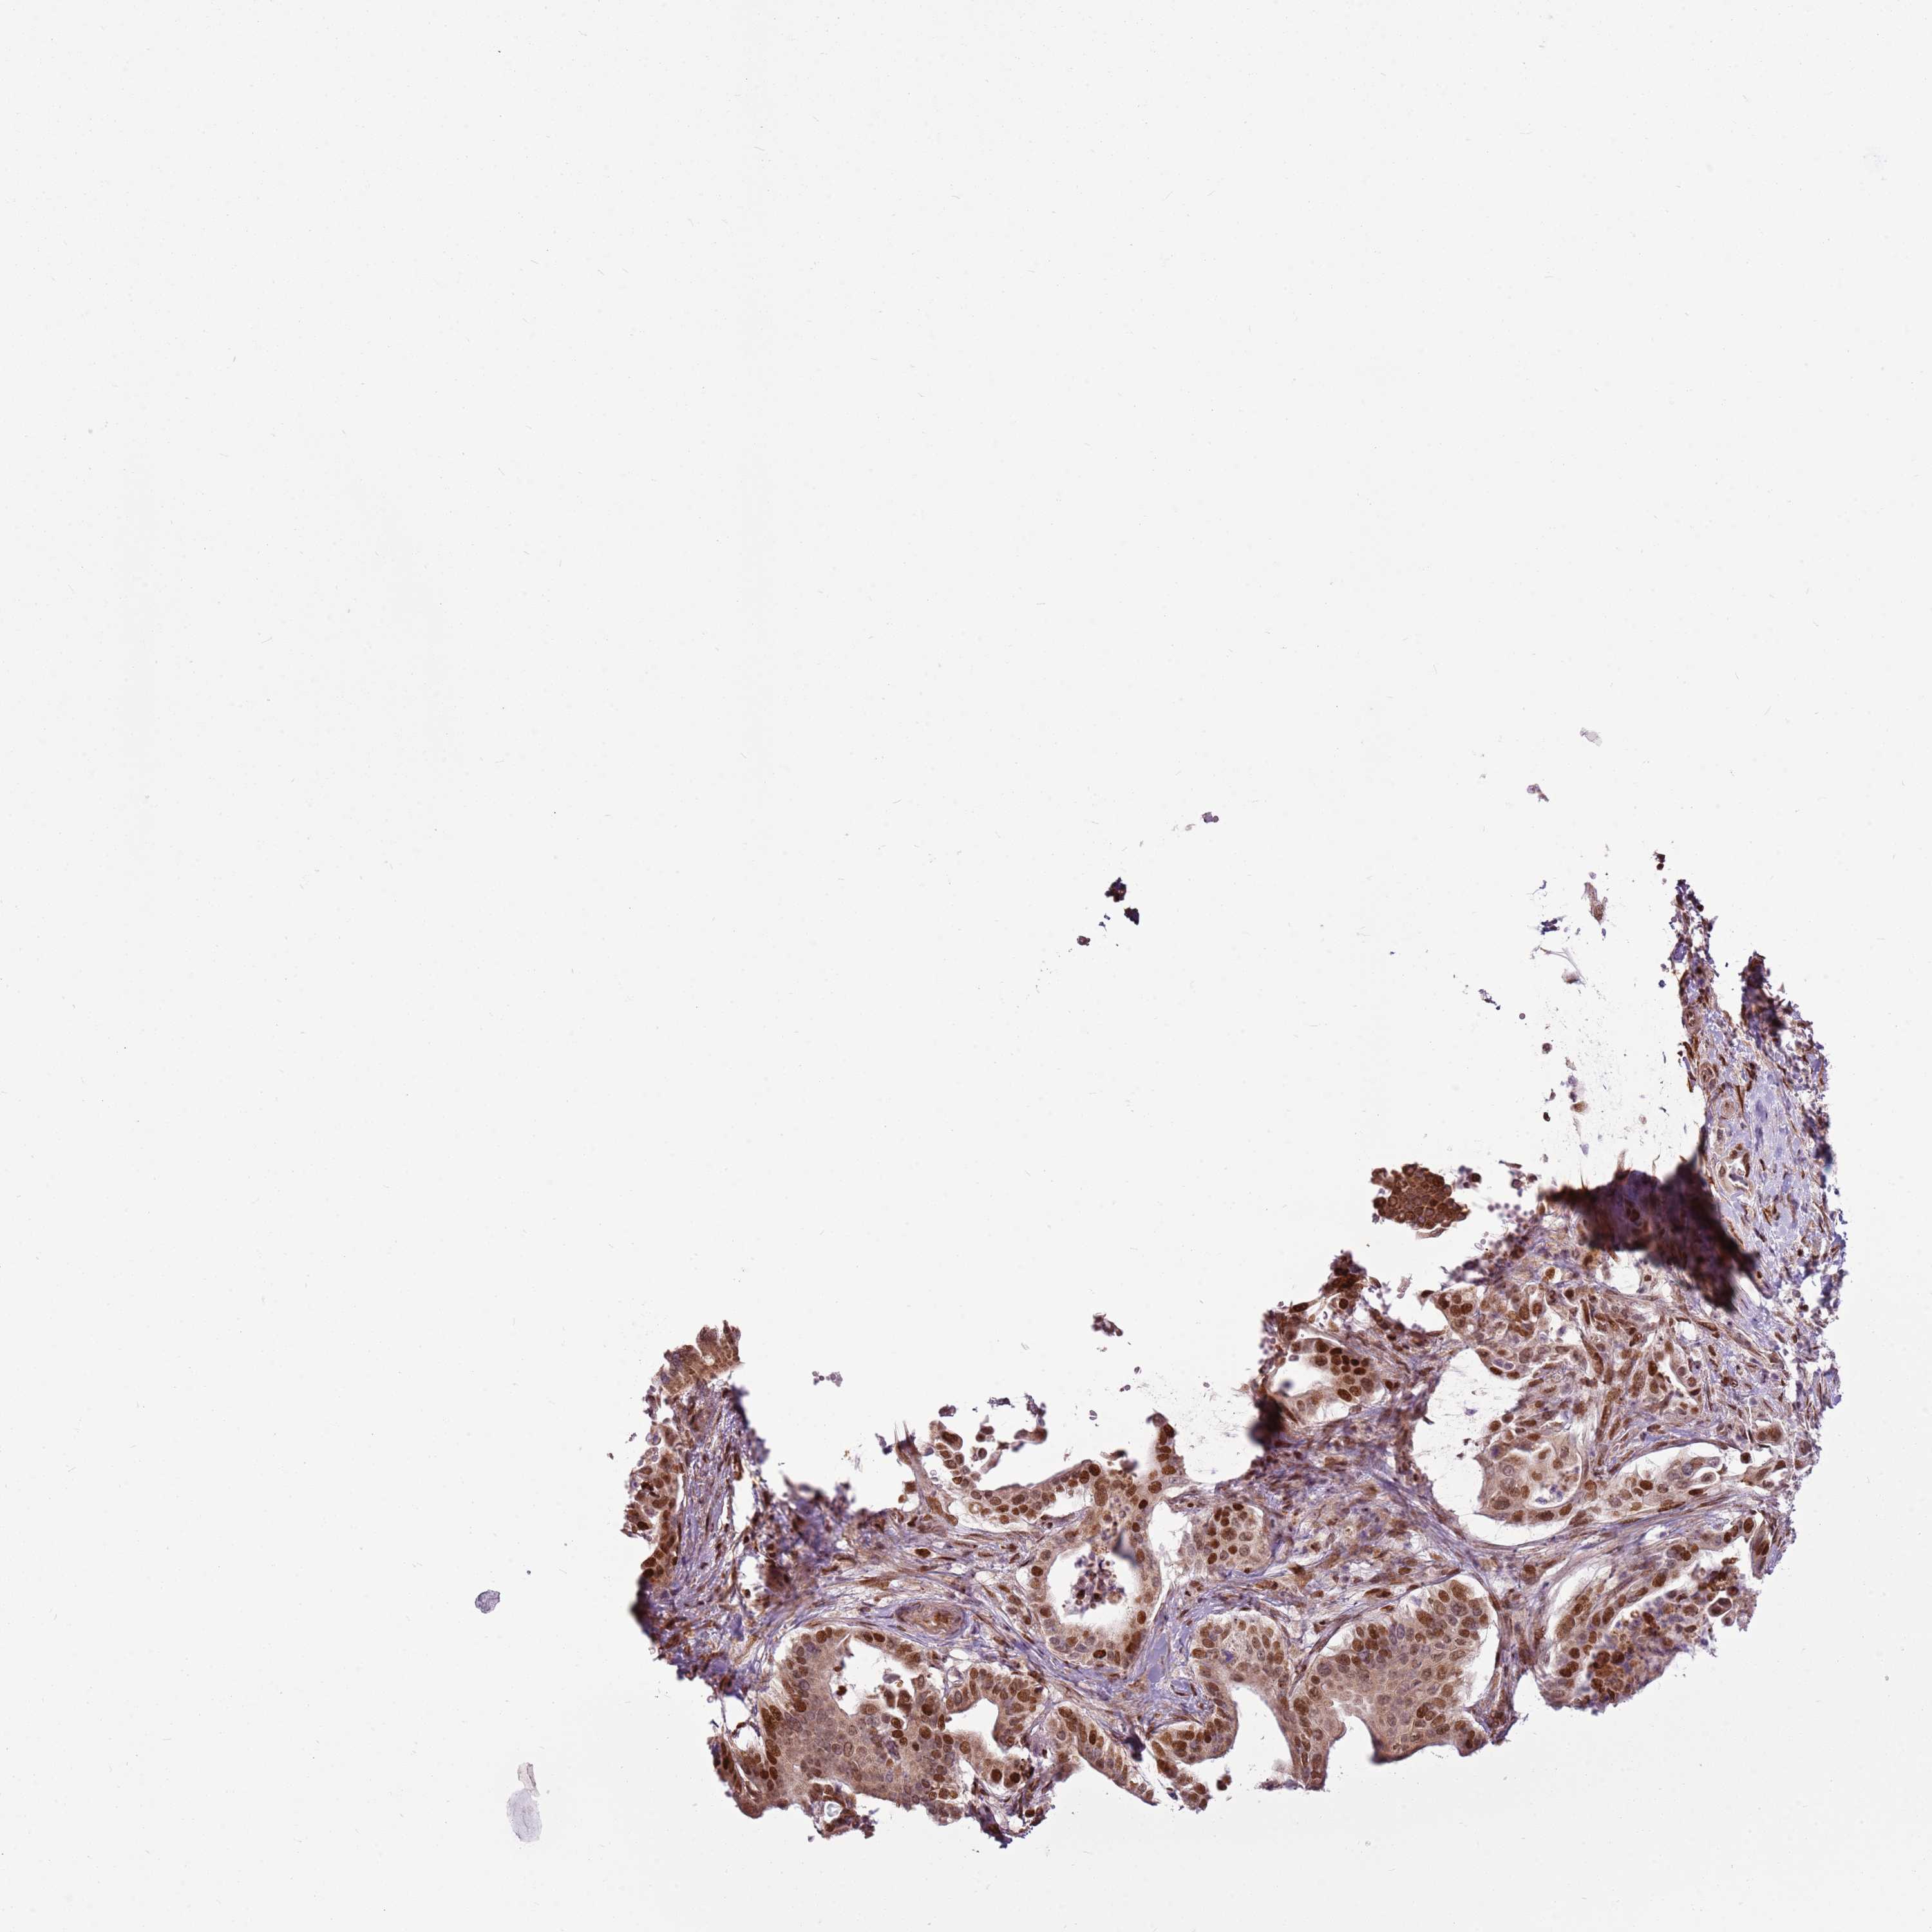

PANCREATIC CANCER - Protein expressioni

A mouse-over function shows sample information and annotation data. Click on an image to view it in a full screen mode. Samples can be filtered based on level of antibody staining by selecting one or several of the following categories: high, medium, low and not detected. The assay and annotation is described here.

Note that samples used for immunohistochemistry by the Human Protein Atlas do not correspond to samples in the TCGA dataset.

Antibody stainingi

Antibody staining in the annotated cell types in the current human tissue is reported as not detected, low, medium, or high, based on conventional immunohistochemistry profiling in selected tissues. This score is based on the combination of the staining intensity and fraction of stained cells.

Each image is clickable and will lead to virtual microscopy that enables deeper exploration of all samples and also displays staining intensity scores, fraction scores and subcellular localization as well as patient and tissue information for each sample.

Antibody HPA022979

Staining

High

Medium

Low

Not detected

Intensity

Strong

Moderate

Weak

Negative

Quantity

>75%

75%-25%

<25%

None

Location

Nuclear

Cytoplasmic/membranous

Cytoplasmic/membranous,nuclear

Adenocarcinoma, NOS